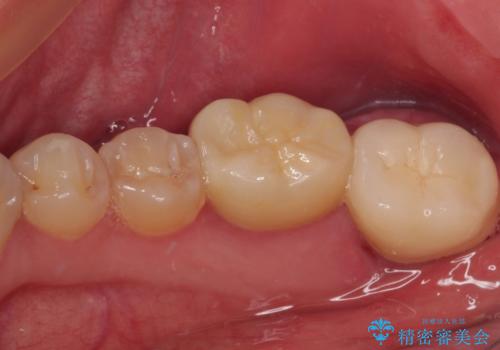

虫歯は歯髄組織のギリギリにまで及んでいたものの、歯髄組織が露出することはなく、処置から数日経った日に行った検査でも歯髄組織の異常所見は認めれらませんでした。

速やかに補綴治療を行い、無事に海外赴任前に治療を終えることができました。